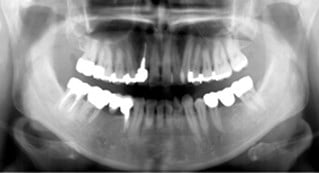

Helkäksröntgen (OPG)

I våra lokaler på Kungsgatan, finns det ett litet rum, "Silvia-rummet", som hyser vår digitala panoramaröntgen: OPG. Med denna röntgenapparat kan vi ta en bild av hela käken på en gång!

Du som patient står upp när bilden tas och du har ingen bildsensor inne i munnen, utan allt sker runt om käkens och huvudets utsida. Tidigare har vi varit tvungna att remittera våra patienter till en röngenspecialist för att få dessa bilder tagna. Panoramaröntgen behövs bl a inför implantatbehandlingar, vid käkskador, för bedömning av käkleder, men också vid förhandsprövningar till Försäkringskassan .

För att öka patientsäkerheten (att kunna hitta dolda tandinfektioner etc) kommer en sådan bild att tas på alla nya patienter vid första undersökningstillfället som en referensbild. Vi vill dessutom ta sådana bilder på samtliga patienter över 40 år som erhållit större fyllningar, genomgått rotbehandlingar - allt som ett led i att, på ett tidigt stadium, kunna upptäcka sjukdomsförändringar i både tänder, käkben och i angränsande vävnader.

Denna typ av röntgenundersökning ersätter inte de årliga s k "bitewings" vi tar för att kunna granska benhöjd och leta efter kariesangrepp med.

Vi tar gärna emot remisser för OPG från andra tandvårdsteam. Bilden är digital och överförs till CD som medium. Behandlande tandläkare ansvarar själv för de eventuella fynd som kan diagnostiseras med hjälp av bilden.